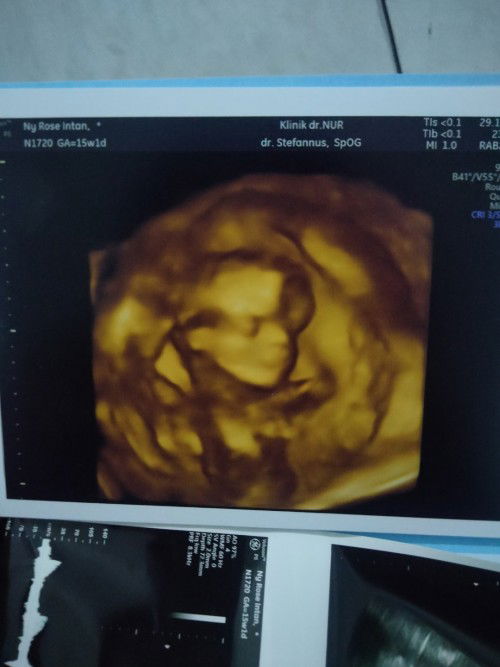

USG 14 week

Masyaallah bund, hari ini saya lagi senang bgt karna abis nengokin dde dalam perut, walaupun antriannya sampe tengah malam tapi kebayar sama dr nya yg ramah bgt, di jelaskan 1/1 dengan jelas, pantas saja banyak ibu antri sampe tengah mlm buat ketemu dokternya 😂😂😂 ternyata seramah itu Oia bund, ini beneran idungnya mancung yaa ? Soalnya yg keliatan jelas cuma idungnya 😂😂😂 Kata dokter air ketubanku keruh bund jadi ga begitu jelas, mungkin gara2 suka minuman dingin kopi dan teh kali yaaaa,, tapi air putihku juga 3L lebih sehari Sehat selalu yaa buat kita smua bundaa